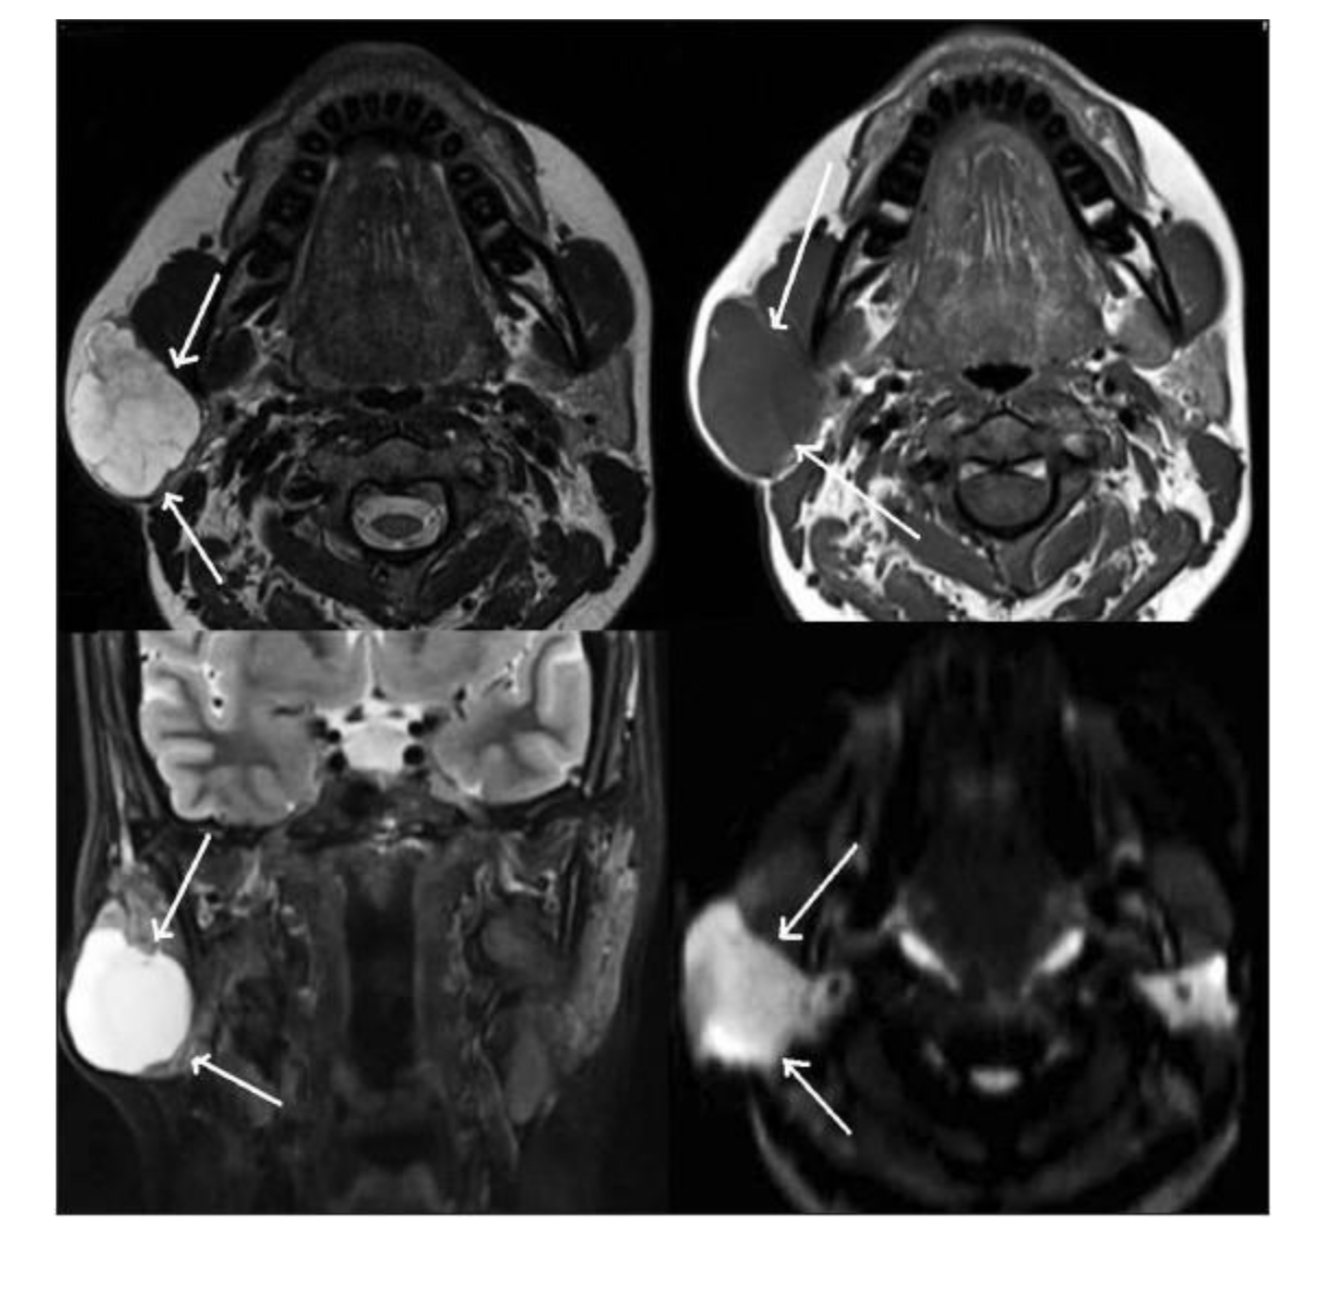

7

Q

What pathology indicated?

A

Mass - right parotid gland

8

What does arrow indicate?

left parotid mass

9

What does arrow indicate ?

submandibular gland

10

Vocal cord Schwannoma